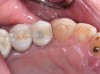

Fig 13. Radiograph depicting peri-implantitis.

Figure 13

Fig 14. Clear resin cement left on the implant abutment.

Figure 14

Fig 15. Implant abutment following cement removal.

Figure 15

If all implant-supported crowns could be designed for screw retention, no discussion of excess cement would be necessary. However, screw retention is not always possible depending on the location of the access opening and because of the unesthetic appearance in anterior restorations or the mesial/distal angulation of the implant compromising the path of insertion (Figure 12). Residual cement left after crown cementation on implants can lead to peri-implant inflammation, peri-implantitis, and eventual loss of the implant (Figure 13 through Figure 15).25 The presence of lingering excess cement can encourage the development of bacterial colonization and peri-implantitis. Conversely, when too little cement is used, voids in the cement layer can occur and the prosthesis can become loose.26 The deeper the implant crown margin, the more difficult it is to remove excess cement.27

Radiopaque cements that contain zinc phosphate and zinc oxide (with and without eugenol) should be considered to help identify excess interproximal cement; however, this should be used secondarily to proper margin height and careful removal of cement during cementation. Resin cements lack the same opacity as zinc-containing cements and have been shown to be the most difficult to remove.28 Often in the process of removing this excess cement, the abutment surface becomes scratched and damaged, potentiating further plaque accumulation.29

Several modifications in abutment design and cementation have been suggested. Placing vent holes in the abutment during fabrication or leaving most of the screw-access chamber open for access has reduced the amount of cement that expresses out into the sulcus.26 It is also beneficial to extraorally express excess cement on an abutment replica prior to final crown seating to minimize complications. If retrievability is desired with cementable implant crowns, weaker cements (eg, zinc oxide eugenol) should be used first and progressively changed until the desired retention is achieved.